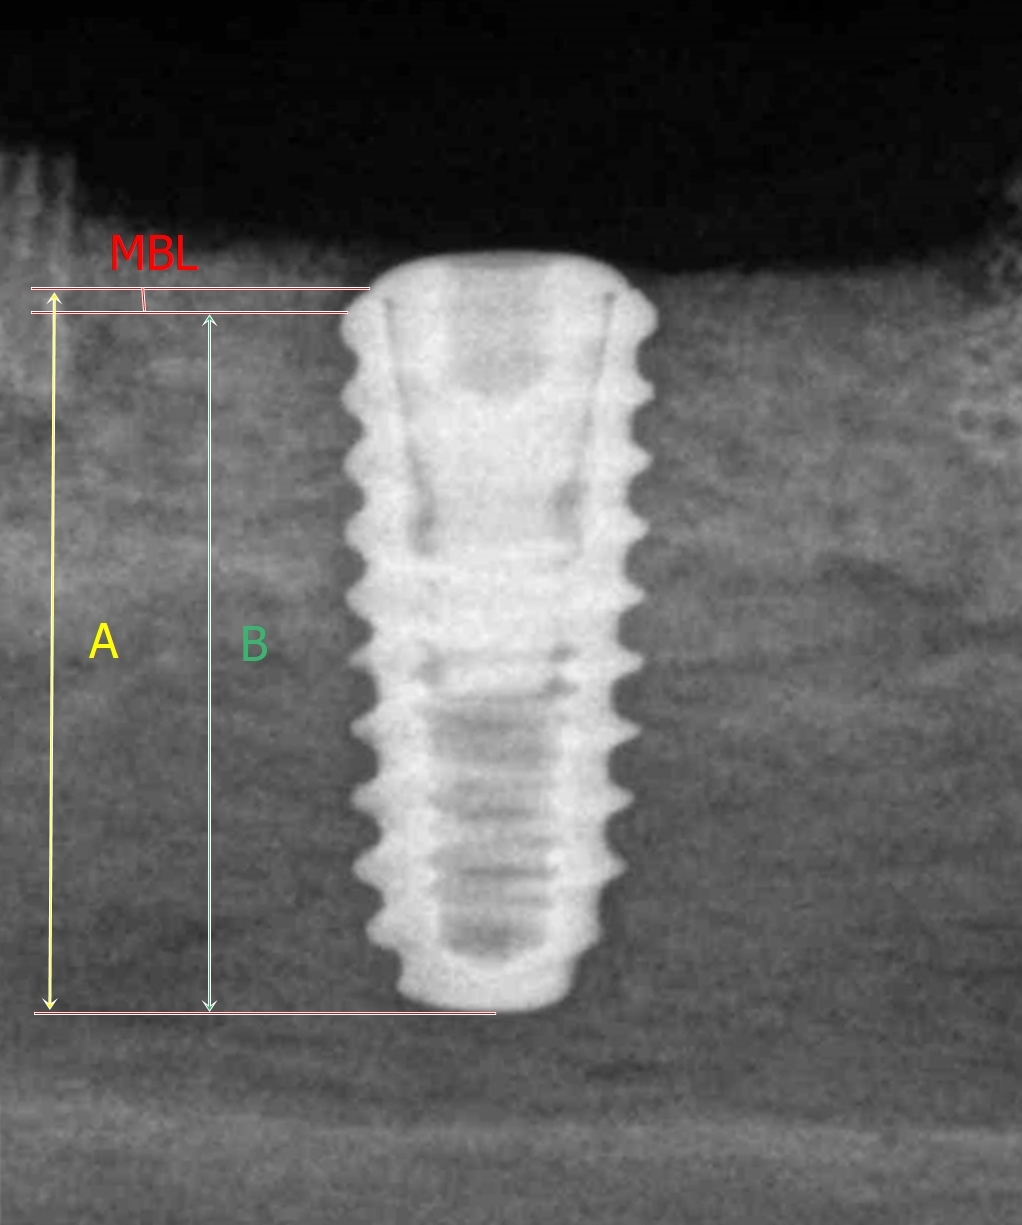

Radiographic images were obtained using a portable dental X-ray unit (DIOX-602; Digimed, Seoul, Republic of Korea) with the parallel technique adapted for excised mandibular beagle specimens. Each specimen was positioned so that the film was parallel to the long axis of the implant fixture, and the X-ray tube was aligned perpendicular to the film from the opposite side. The marginal bone level (MBL) on the radiographic images was defined as the perpendicular distance from the fixture–abutment interface to the implant–bone junction. The length of the implant fixture (IF) was measured as the perpendicular distance from the fixture–abutment interface to the apex of the fixture. The MBL was measured on the mesial and distal sides of each implant using the same radiographic images (Fig. 6). Measurements were performed independently by each examiner on individual computers using ImageJ software (National Institutes of Health, Bethesda, MD, USA). Each examiner identified the alveolar bone level and drew reference lines corresponding to the fixture length and bone level, as illustrated in Fig. 6, then calculated the actual MBL according to the following formula:16, 17

Fig. 6

Radiographic image showing marginal bone level (MBL) measurements at mesial and distal sites. “A” indicates the measured length from the fixture–abutment interface to the end of the implant fixture, and “B” indicates the measured length from the implant–bone junction to the end of the implant fixture.

Actual MBL=Measured MBL/Measured length of the IF x Actual length of the IF

This procedure ensured that the assessment of bone loss and the subsequent calculation of MBL were performed consistently across examiners, allowing evaluation of interrater reliability for the radiographic analysis (Table 2).